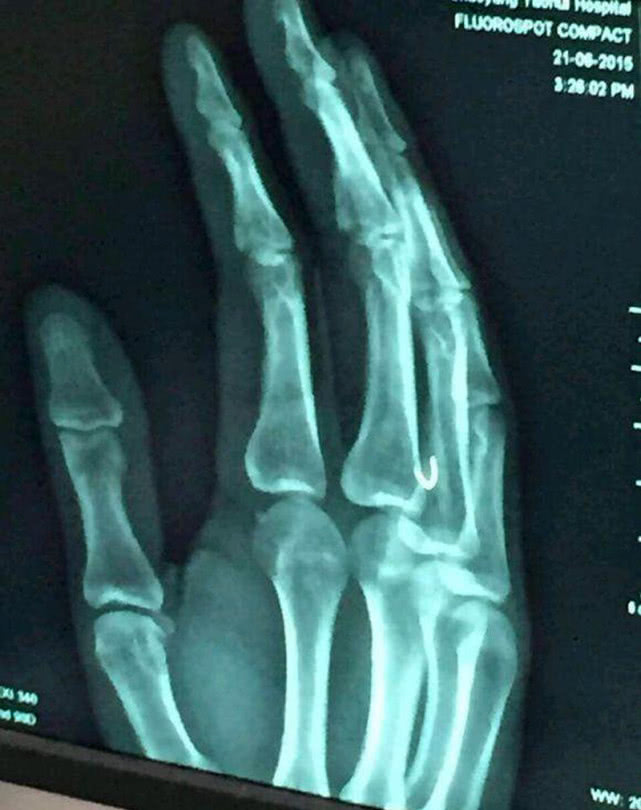

等我把鱼溜翻白了,也顺利的抄鱼上岸了。可就在我放松警惕摘钩时,鱼却突然向外窜,绷紧的鱼线突然弹了回来,一不小心把钩子挂在了自己的手指上。鲜血马上渗出,疼痛难忍,无论如何,却不能取出,因为倒刺已经深入肌肉组织,如果硬拔,要将手指内肌肉组织带出,更是像割肉一样,疼痛啊,眼泪也出来,一时也不能去医院(路远),没有办法。

倒刺鱼钩挂在手上千万别往外拔,人的皮是很厚滴,倒刺挡着根本不可能拔出来,挂上后千万别慌,不要沾到生水,把钩上的线剪断,清除钩把上残留的线头,然后直接捏住钩顺着钩尖的方向穿透皮肤,因为鱼钩是U型的,很容易就穿过来了,鱼钩取出后,用力挤出脏血,直到血液鲜红为止。用干净的棉布或者纸巾包扎,回家后用药物消毒,服用抗生素。虽然创伤小,但也痛,但总比用刀划开强,如果钩把比较大或有圆环等其他大的阻挡的话,用斜口钳剪断钩柄,穿透取出,取出后注意消炎。

之前也有看到钓友被鱼钩刺手,深入到骨头之中了,去医院,医生给划了个2~3公分口子,还缝了3~4针。想想去医院除了手疼还会心疼就自己处理了。如大家有更好的方法请贡献出来,钓鱼人谁没被挂过啊。